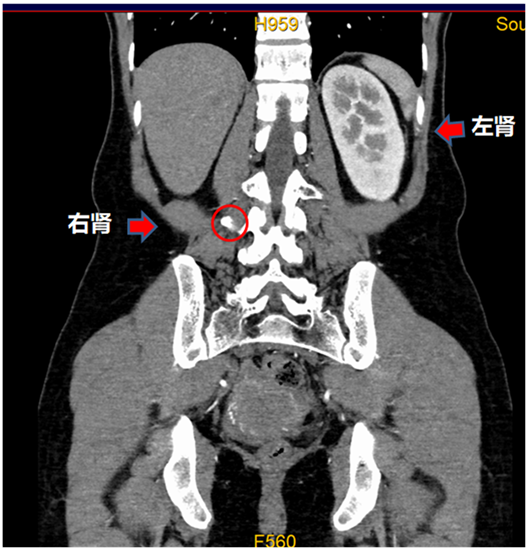

在醫學影像中心,王小姐一躺上去,技師王金電就看到了異常。正常人的腎臟如芒果大小,左右各一,安分地掛在腎區,但是王小姐只有一個左腎,右腎區域一片空白。「獨腎」對影像人來說很常見,大多數人沒有什麼症狀,但王金電瞄了一眼,看到王小姐有「漏尿」,於是多留了個心眼,在腰大肌的旁邊,他敏銳地捕捉到了一個小小的「閃光點」,大小只有正常腎的二十分之一。原來,右腎並沒有憑空消失,而是跑到了盆腔。

這個檢查結果終結了王小姐32年「獨腎」的歷史,幫她找到了傳說中的「右腎」和那根連到陰道里的輸尿管,至此,謎團被揭開:右腎發育不良,右腎異位,右側輸尿管異位開口。